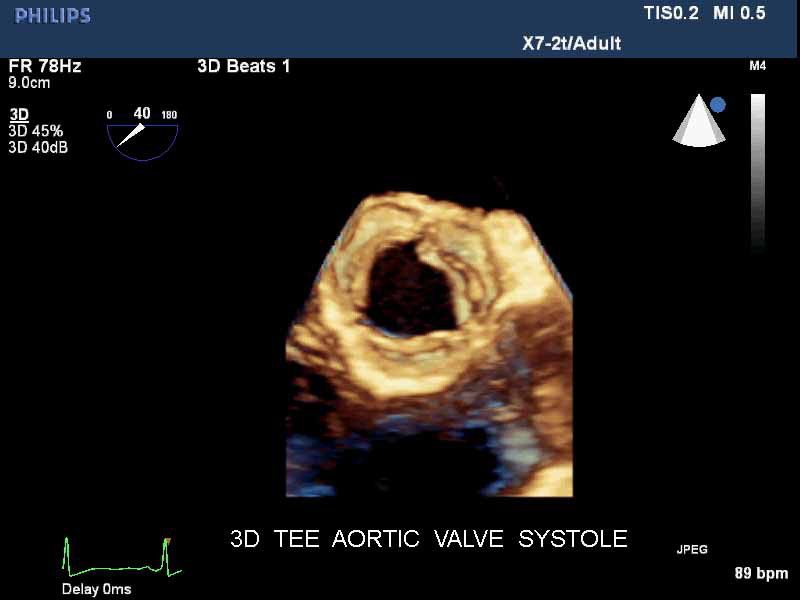

• Live 3D TEE: Эта функция позволяет проводить чреспищеводную эхокардиографию в режиме реального времени, что позволяет оценить механические сокращения сердца с точностью, необходимой для оценки результатов хирургического вмешательства.

• Чреспищеводная эхокардиография

• Чреспищеводный УЗИ датчик Philips Х7-2T